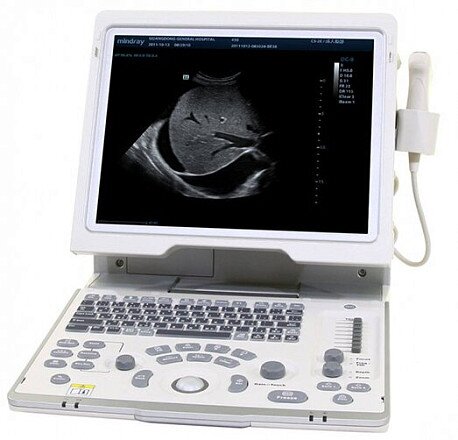

Клинические изображения

Mindray DP-50 - цифровая черно-белая ультразвуковая система портативного типа, оснащенная жидкокристаллическим широкоугольным монитором с диагональю 15 дюймов и возможностью изменения наклона для улучшения обзора и удобства врача. УЗИ сканер может работать от аккумулятора, а также от сети. Отличаясь компактными габаритами и имея сравнительно небольшой вес (всего 7,5 кг), легко размещается в помещениях с ограниченным пространством.